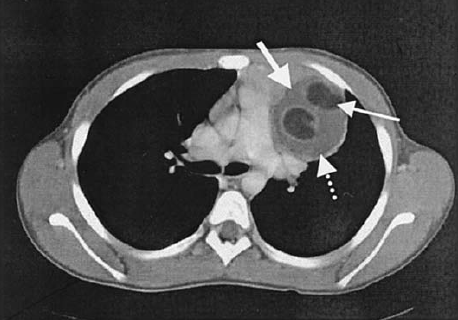

• Bronxial sistlərin əksəriyyəti bronxətrafı sahədə yerləşir, divarında bronxial epitel və tərkibində bəzən qığırdaq görünür (Şəkil 22).

• Bronxial və enterik sistlərin diaqnozu adətən çıxarıldıqdan sonra dəqiqləşir. Perikardial sistlərin diaqnozu görüntüləmə ilə dəqiqləşdirilə bilir (Şəkil 23), lakin diferensiasiya çətinliyi və simptomatik olanlarda cərrahi eksiziya lazım gəlir.

Şəkil 22. KT. Bronxial sist

Şəkil 23. KT. Perikardial sist